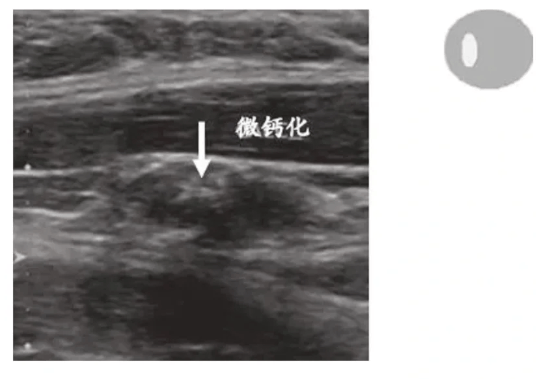

①微钙化(特异性最高)

多见于甲状腺乳头状癌转移淋巴结,表现为散在或簇状点状强回声(直径<2mm),后方无声影,对应病理上的砂砾体,乳头状癌转移风险>90%!